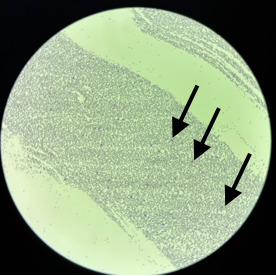

さらに、リンパ球が腫瘍性のものであるかどうかも確認しました。

低倍率像。

矢印で示した濃い紫色の点状に見えるのが白血球ですが、そのほとんどがリンパ球です。

高倍率像。

オレンジ色の矢印は正常リンパ球、赤色の矢印は腫瘍性リンパ球、矢印がないのは好中球です。視野に映る白血球のうち、大半が腫瘍性リンパ球であることがわかります。